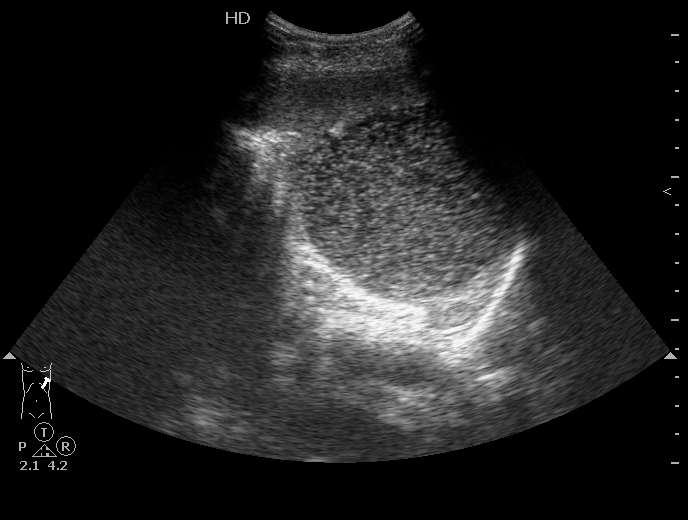

Сегодня задренировал, содержимое - см. фото

Цитология: белковый преципитат, большое количество эритроцитов, лейкоцитов 5-8 в поле зрения.

Таким образом, видимо, в нашем случае это посттравматическая киста.

Дренаж удален на 4-й день, через трое суток при контрольном УЗИ - киста прежних размеров.